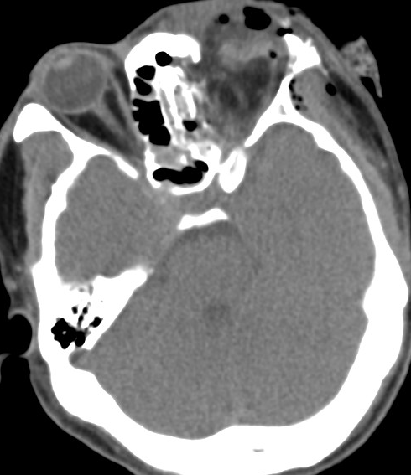

2014-10-5 CT